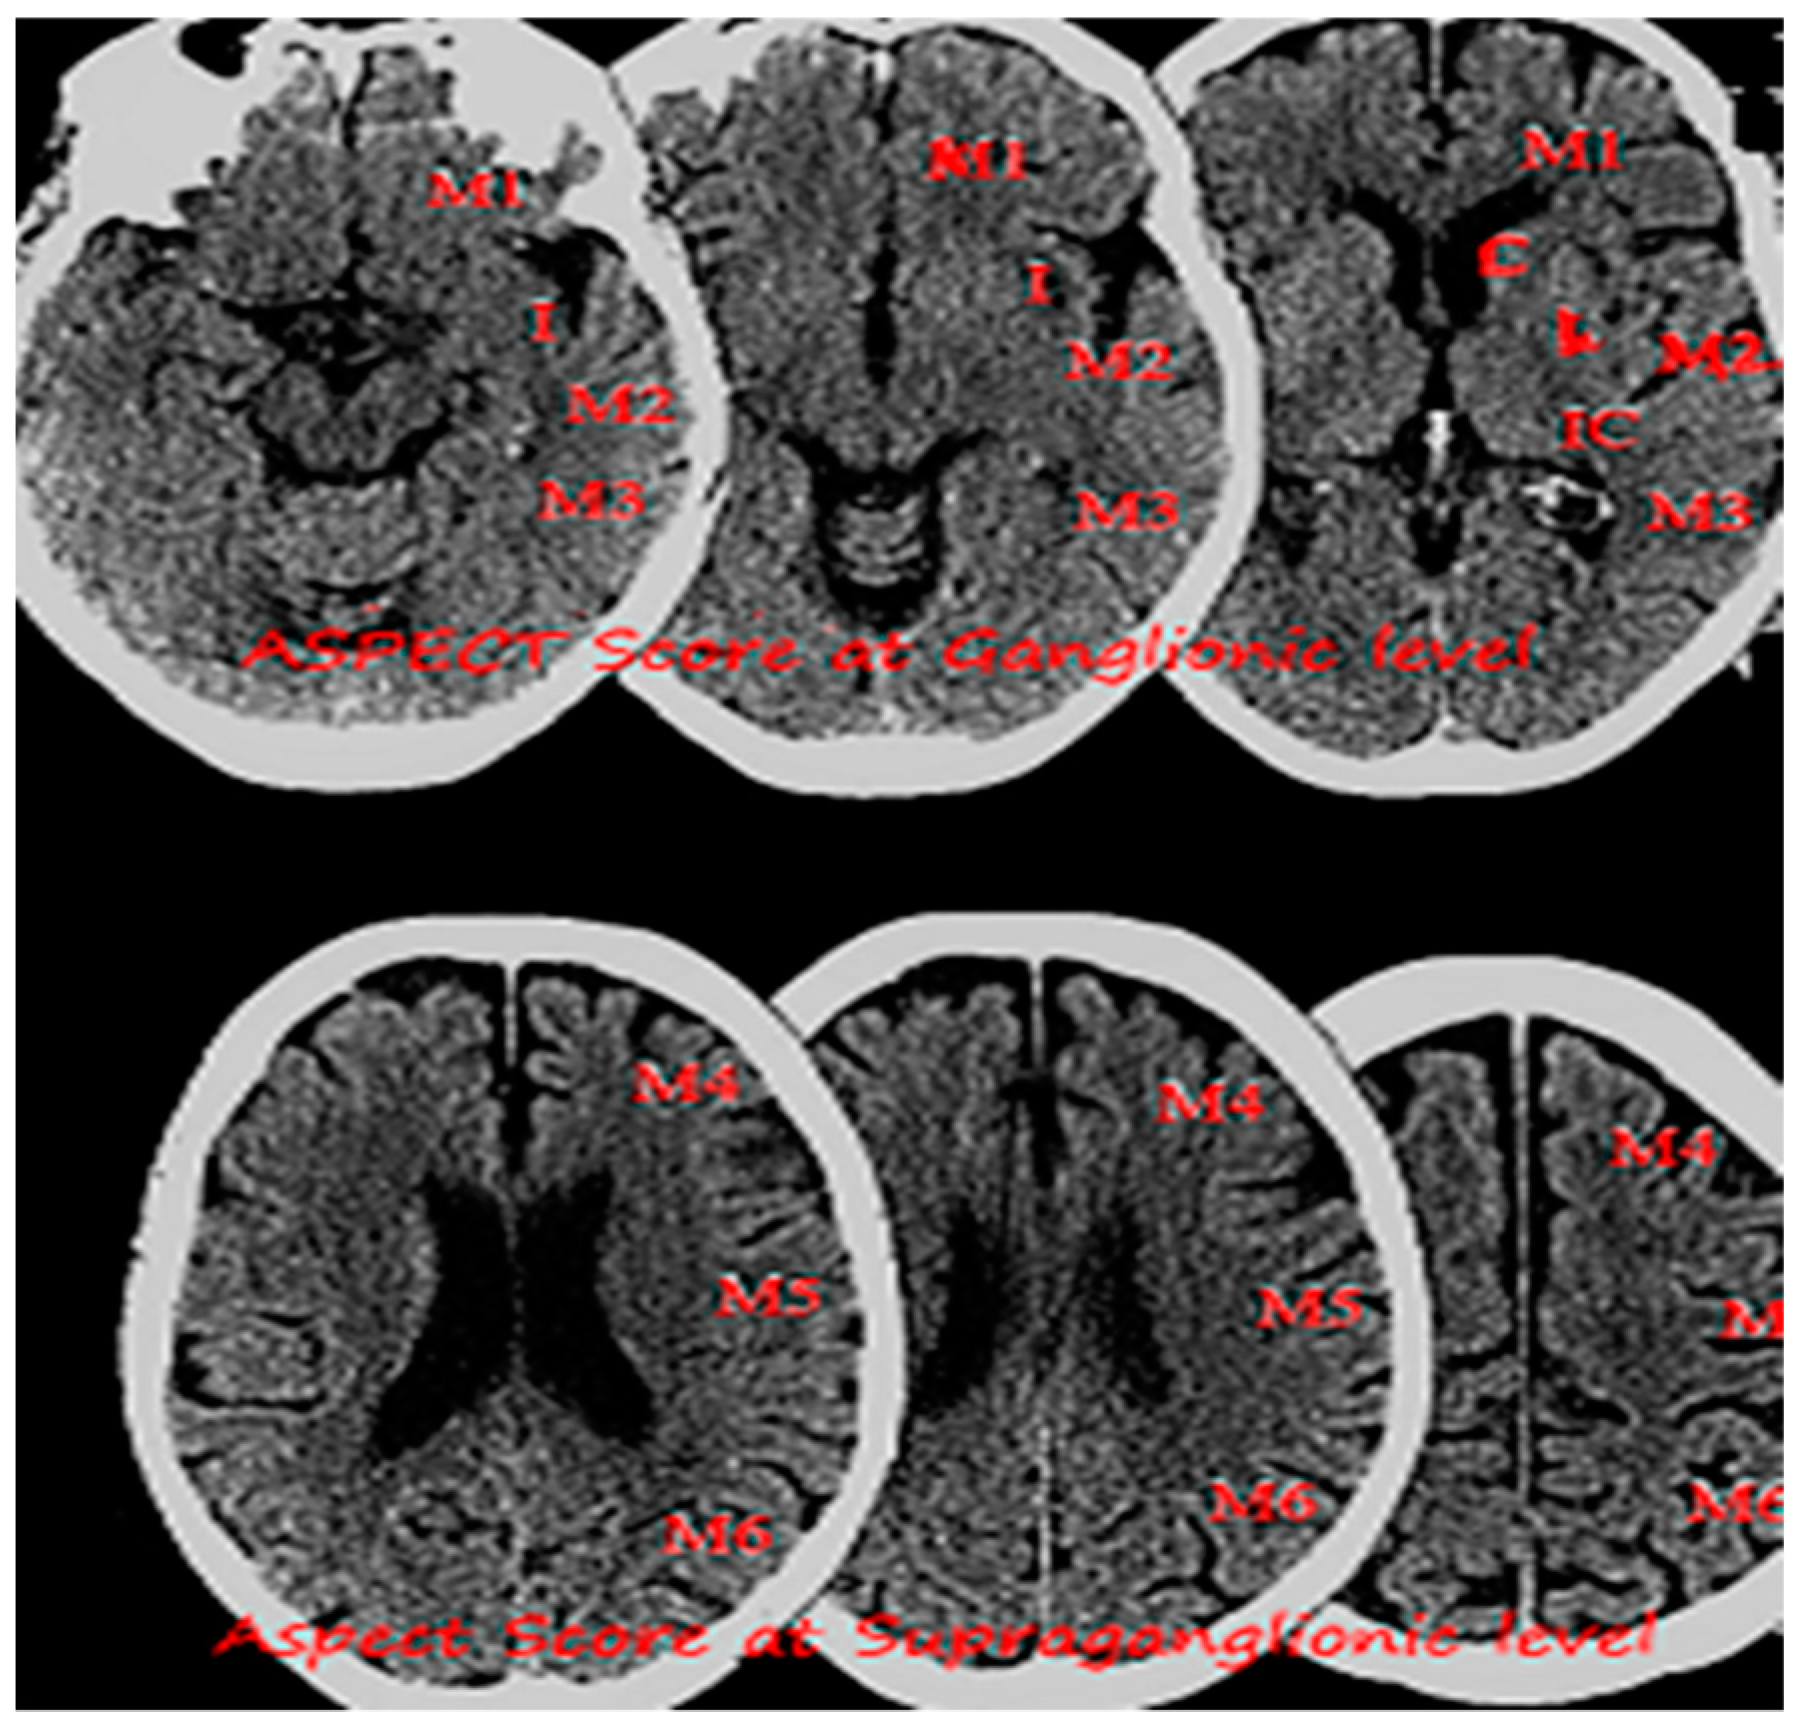

- Barber, P.A.; Demchuk, A.M.; Zhang, J.; Buchan, A.M. Validity and reliability of a quantitative computed tomography score in predicting outcome of hyperacute stroke before thrombolytic therapy. ASPECTS Study Group. Alberta Stroke Programme Early CT Score. Lancet 2000, 355, 1670–1674. [Google Scholar] [CrossRef]